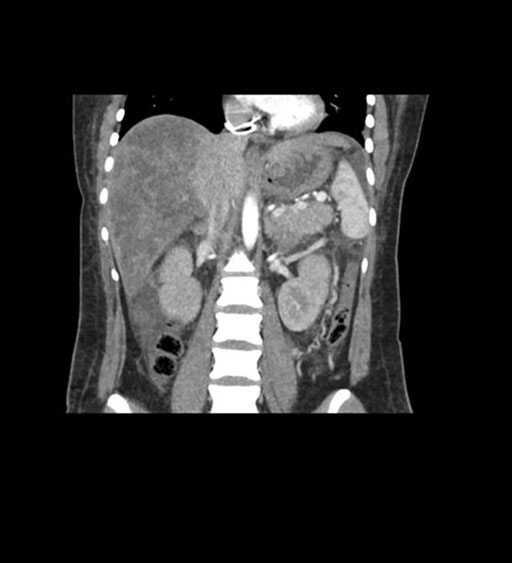

Coronal Arterial

Coronal Venous